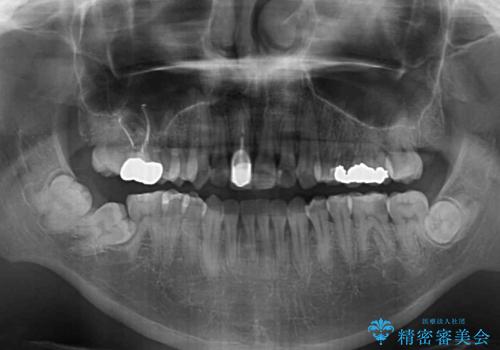

- 前歯のデコボコと上下のクロスバイトを気にして来院された患者様です。

インビザラインを用い、IPR(歯と歯の間を削る)と歯列全体を拡大させることで、歯並びを整えていくこととしました。

上の前歯が下の前歯を乗り越える際、奥歯がほとんど咬めない時期があり、乗り越えた後も、インビザライン特有の奥歯の咬みにくさが続きました。

咬み合わせ改善のために治療期間を要しましたが、最終的に奥歯はしっかりと咬めるようになりました